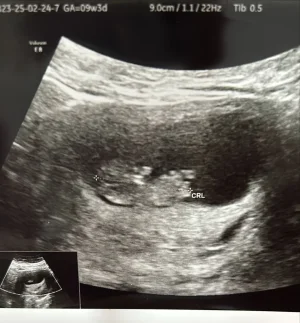

bizde bu gun 9 haftalık olduk

sadece kesem ilk ultrasonda fasuyle gibiydi. Ona erkek diyorlar ama herkeste aynımı bilemem